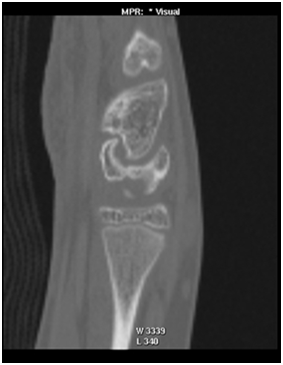

The X-rays showed the presence of a large bone tumour arisen from the lunate bone, not showing the actual involvement of the tumour in the carpal joints (Figure 2A); the subsequent CT scan confirmed the more accurate extension of the mass showing how the osteochondroma expanded dorsally and proximally, reducing and invading the ulno-carpal space (Figure 2B &2C), and also in the lateral view was easy to see how the deformed lunate had an expansion of the volar rim up to the neck of the capitate, reducing the midcarpal motion as well (Figure 2D).

Figure 2B & C 3D CT scan of the Lunate osteochondroma

Figure 2D Lateral view showing the extension of the volar rim of the Lunate  up to the neck of the Capitate.